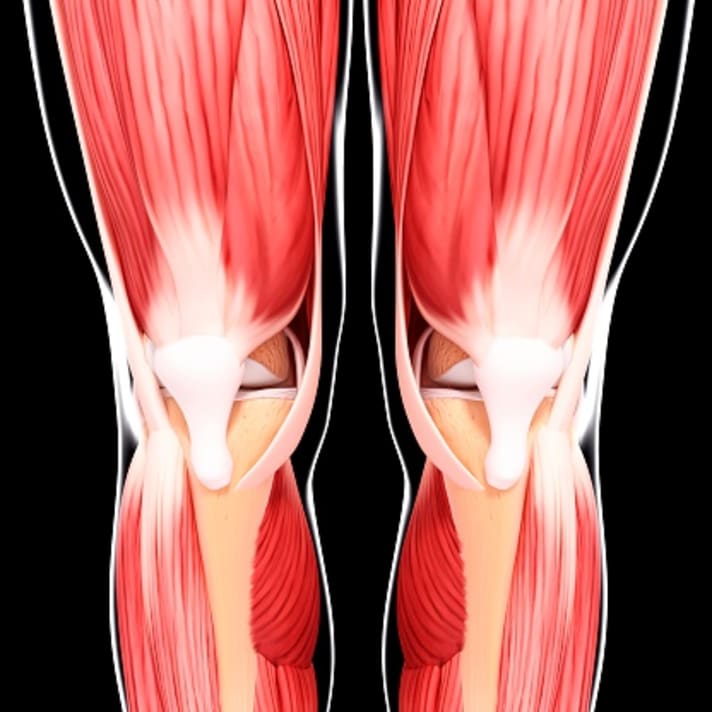

The leg is never fully extended when cycling. This can lead to muscular imbalances. Especially when these imbalances develop and the leg axis is not optimal, as is the case with knock knees or bow legs, the likelihood of incorrectly loading the knee increases. Due to the lack of knee extension, the outer thigh is activated more than the inner thigh. The higher muscle tension on one side can cause the kneecap to shift outwards, for example. Bikers notice this when riding with clipless pedals, for example, due to pain on the outside of the knee joint.

The muscles in the leg should all be trained, and in a balanced way. Of course, there is an adaptation to the type of sport. However, if the differences become too great, consequences will occur. The five pillars of fitness are endurance, strength, flexibility, coordination and speed. If I want to win races, I usually need the endurance component a lot. Nevertheless, I have to train all facets if I want to take preventive action. Most cyclists don't like to stretch. Mobility is often neglected, as is strength training. You get the necessary coordination from cycling itself, although it also helps to set other stimuli. Speed results from the combination of coordination and strength.

Which muscles should I train and how should I train them to preventively prepare my knee for mountain biking?

To counteract the one-sidedness of cycling, mainly the inner part of the quadriceps should be strengthened, while the outer and rear parts in particular should be stretched repeatedly. However, stretching alone is not always effective enough. It is better to combine flexibility exercises with fascia and strength training.